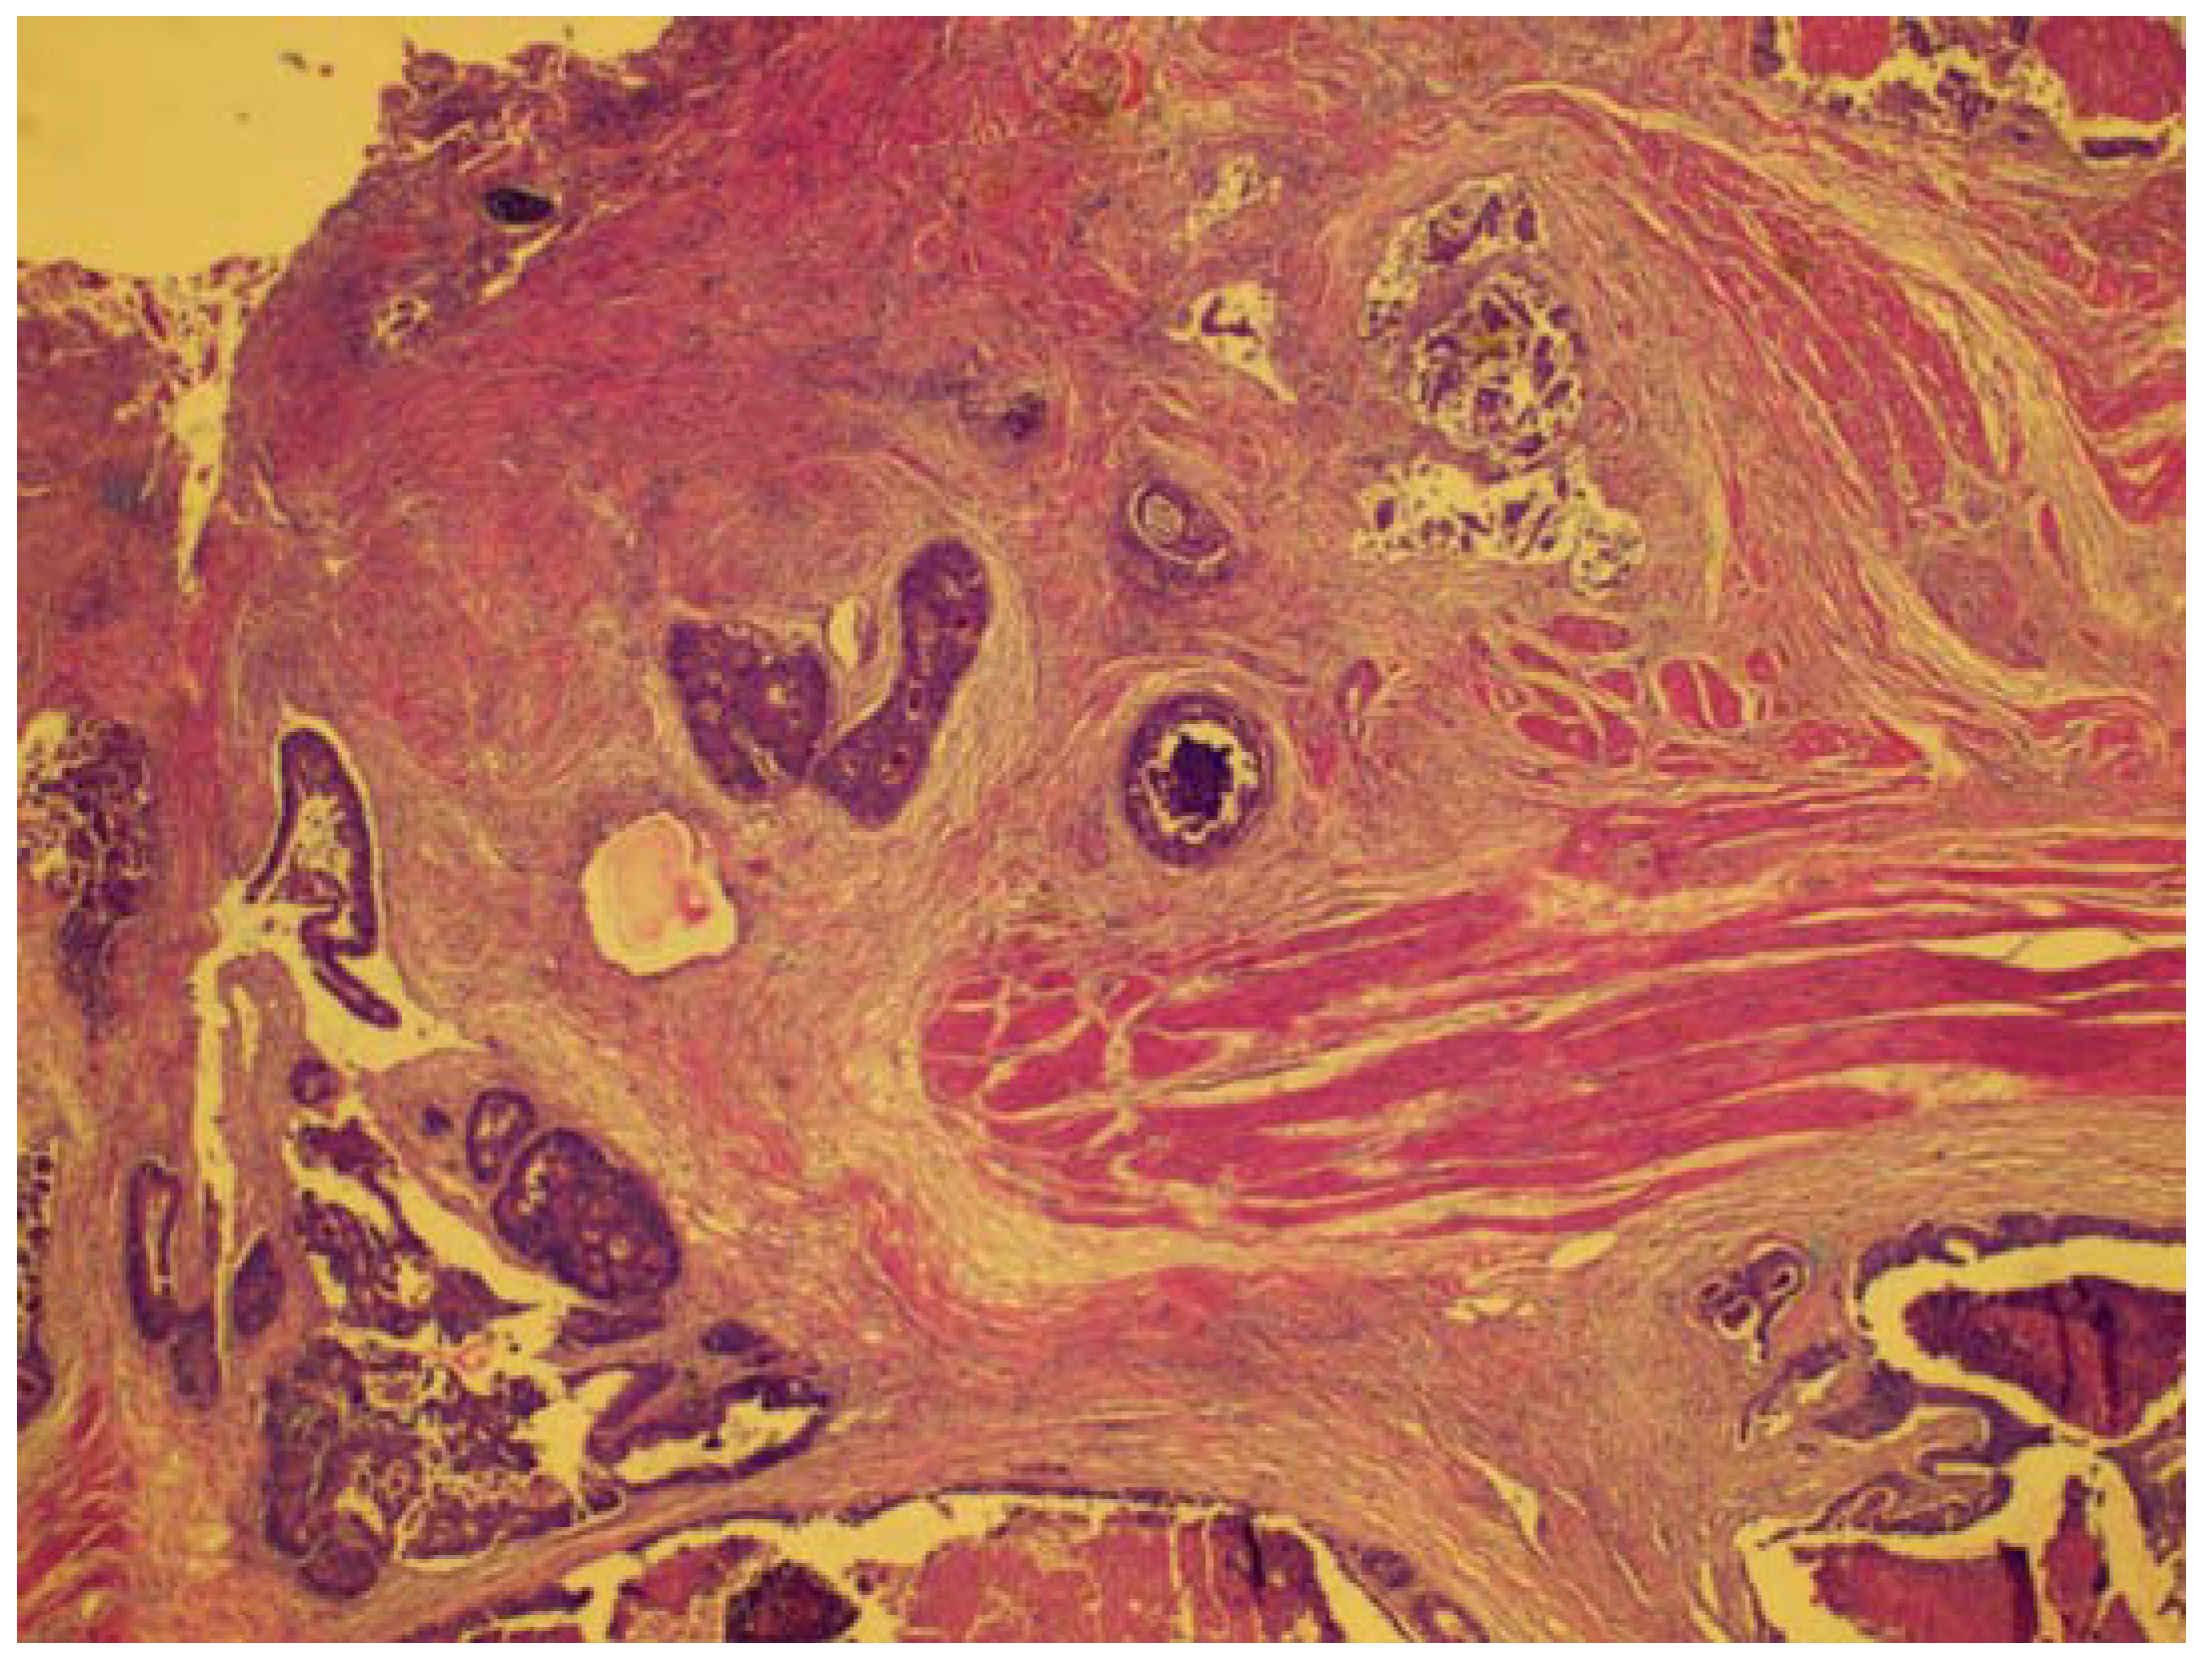

Figure 1. A rectal wall with ulcerated mucosa (top) and tumor islands infiltrating into the muscular propria layer.